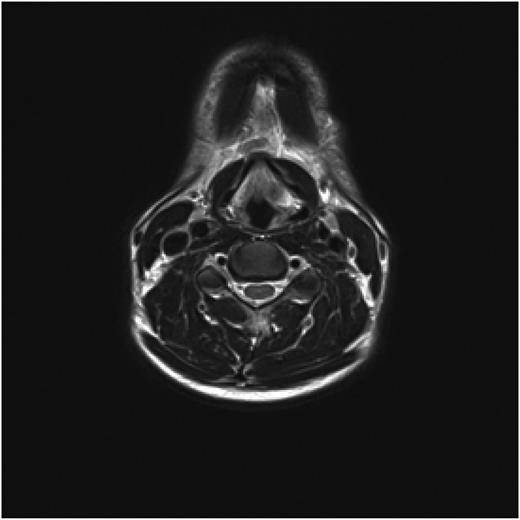

Post treatment with CO2 laser, the patient underwent a T1 weighted magnetic resonance imaging (MRI) with gadolinium of the neck. The imaging demonstrated an abnormal soft tissue density in the left supraglottic region (Figs 3 and 4). The low intensity lesion was 9 × 4 mm in size and caused distortion of the left aryepiglottic fold and minor airway narrowing. The findings on MRI suggested the persistence of disease.

Axial view of MRI neck demonstrating soft tissue abnormality in the left supraglottic area.